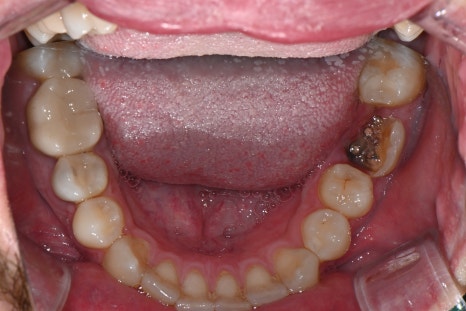

These are intraoral photos of the upper and lower teeth taken at the time of the visit.

Due to the loss of the second small molar on the upper right, implant treatment was needed.